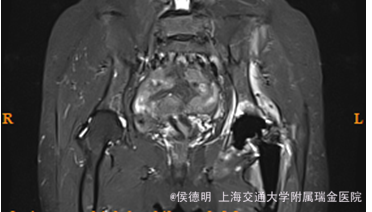

主诉:左髋关节术后疼痛4月余 病史:患者,女,63岁。患者1年前因摔倒致左髋疼痛,活动受限,无法行走。当时无明显眼花、头晕,无呕吐,无胸腹痛,无颈项强直,病理征未引出。随即至外院就诊,摄X片示左股骨颈骨折,并行“左全髋人工关节置换术”,术后伤口愈合良好。患者于3月前出现左髋疼痛,外院就诊查ESR95mm/h,CRP52.5mg/L,患者目前出现髋关节疼痛,静息痛和活动后疼痛都较明显。遂前往我院门诊就诊,行假体MRI示假体周围异常信号,多发淋巴结显示,行同位素扫描提示假体周围血流增高,炎性可能。故门诊拟诊“左髋关节术后感染可能 ”收住入院。

查体:左侧髋关节周围组织未见明显肿胀及发红,左髋伤口疤痕愈合好,局部皮温不高。左髋关节活动受限.左侧髋纵向叩击痛(+),右下肢无外旋、无明显缩短畸形,两下肢皮肤感觉无异常,病理征未引出。 辅检: 1.左髋MRI:左髋关节置换术后改变;股骨上段、髋臼及髂骨及周围软组织异常信号;双侧腹股沟内多发淋巴结显。 2.骨盆正位片:左侧髋关节置换术后改变,关节在位。周围软组织略肿胀。